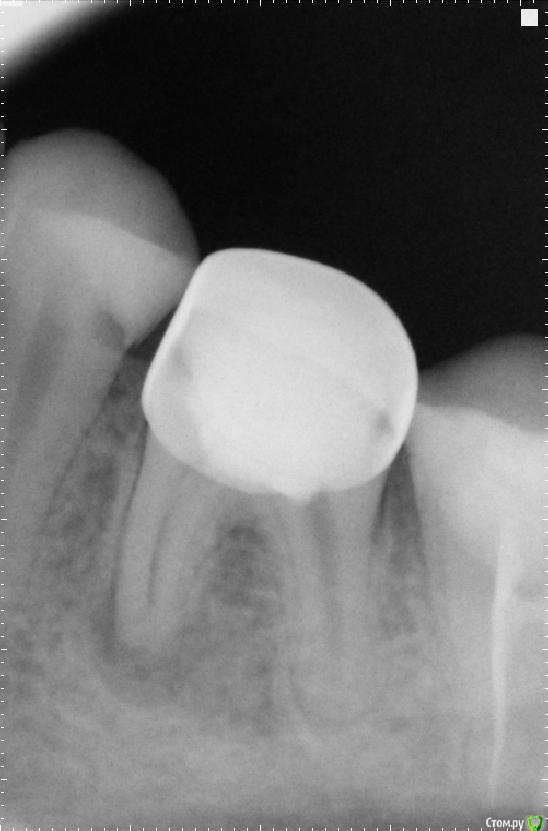

Сашуля Опубликовано 8 декабря, 2016 Поделиться Опубликовано 8 декабря, 2016 (изменено) Здравствуйте уважаемые стоматологи.Очень хочется получить совет.Имею хронический периодонтит. Температура 37,3 постоянно, впрочем, это мне не мешает.Первое фото. Когда обнаружили периодонтит. 2013 год.Второе фото-в процессе лечения.Мне запломбировали каналы, постави вкладку, налили пластиковую временную коронку и отправили в свободное плавание. Зуб никак не беспокоил.Наблюдалась, делала снимки с определённой периодичностью. Зуб не беспокоил.Сейчас настал решающий момент. Последние два снимка были сделаны сегодня. Сторона с проблемным зубом ноет, непонятно, что это болит, толи соседние зубы, толи периодонтит беспокоит. Боль усиливается к вечеру. При надавливании на проблемный зуб острая боль. При внешнем осмотре всё в норме.Вообще грозятся удалять или сделать Гемисекцию. Чего мне ожидать, может быть можно по данным снимкам чтото выяснить.Спасибо. Изменено 8 декабря, 2016 пользователем Сашуля Ссылка на комментарий

DmitrySH Опубликовано 8 декабря, 2016 Поделиться Опубликовано 8 декабря, 2016 Последний снимок не четкий. Видимо нужна ревизия каналов. Еще 5тый зуб, кариес под пломбой 1 Ссылка на комментарий

IvanK Опубликовано 8 декабря, 2016 Поделиться Опубликовано 8 декабря, 2016 Последний снимок выглядит не плохо, я бы сделал кт скорее всего у Вас пульпит 5го Боль усиливается к вечеру. 1 Ссылка на комментарий